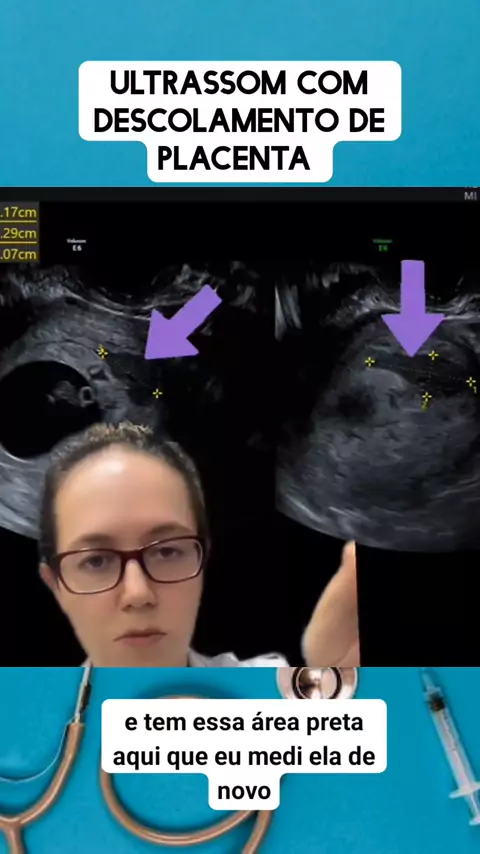

ultrassom obstetríca descolamento de placenta #medico #medicina #Saúde #viraliza